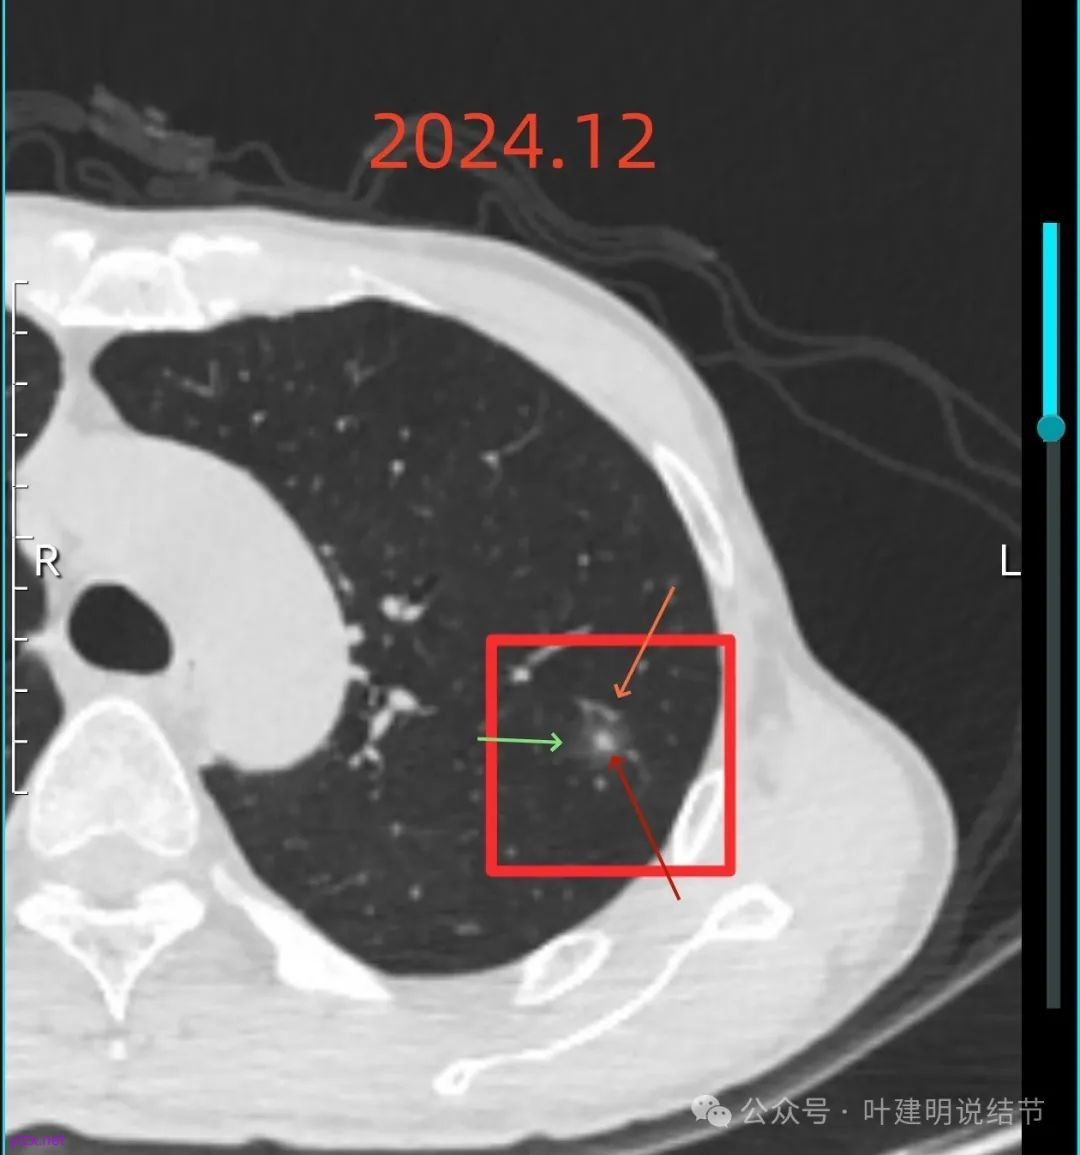

再来看2024年12月时的影像:

右下实性结节两年来没有变化,那它就是良性的可能性大些了,至少目前不考虑干预处理。

右上混合阴影也没有明显进展,则同样要更倾向确实是支气管扩张伴慢性炎与纤维增生的关系,可随访。

左上病灶血管进入了病灶且有异常增粗,边缘有淡的细毛刺的样子。

灶内血管明显,管壁略毛糙,有异常增粗,红色箭头处有点状高密度,边缘有毛刺征。

灶内出现了明显的实性成分,整体轮廓较清。

除了原血管进入外,另外角度也见到其他血管发出分支走向病灶,而且灶内密度不均,实性成分明显。

绿色的像是慢性炎,随访没有进展;红色的2022年12月开始是纯磨玻璃密度,但有小血管进入和整体轮廓较清,这种密度风险不高,但随访持续在的话,则要考虑肿瘤范畴,不典型增生或原位癌可能性大。再看2025年12月的,范围有所增大,磨玻璃部分密度仍很淡,但灶内出现实性成分,实性成分不太密实,稍显模糊。我觉得像微浸润性腺癌或原位癌伴肺泡塌陷可能性大。位置还好,病灶也不太小,若再增大进展切除范围更多些,我倾向单孔胸腔镜下局部楔形切了为妥。意见供参考!